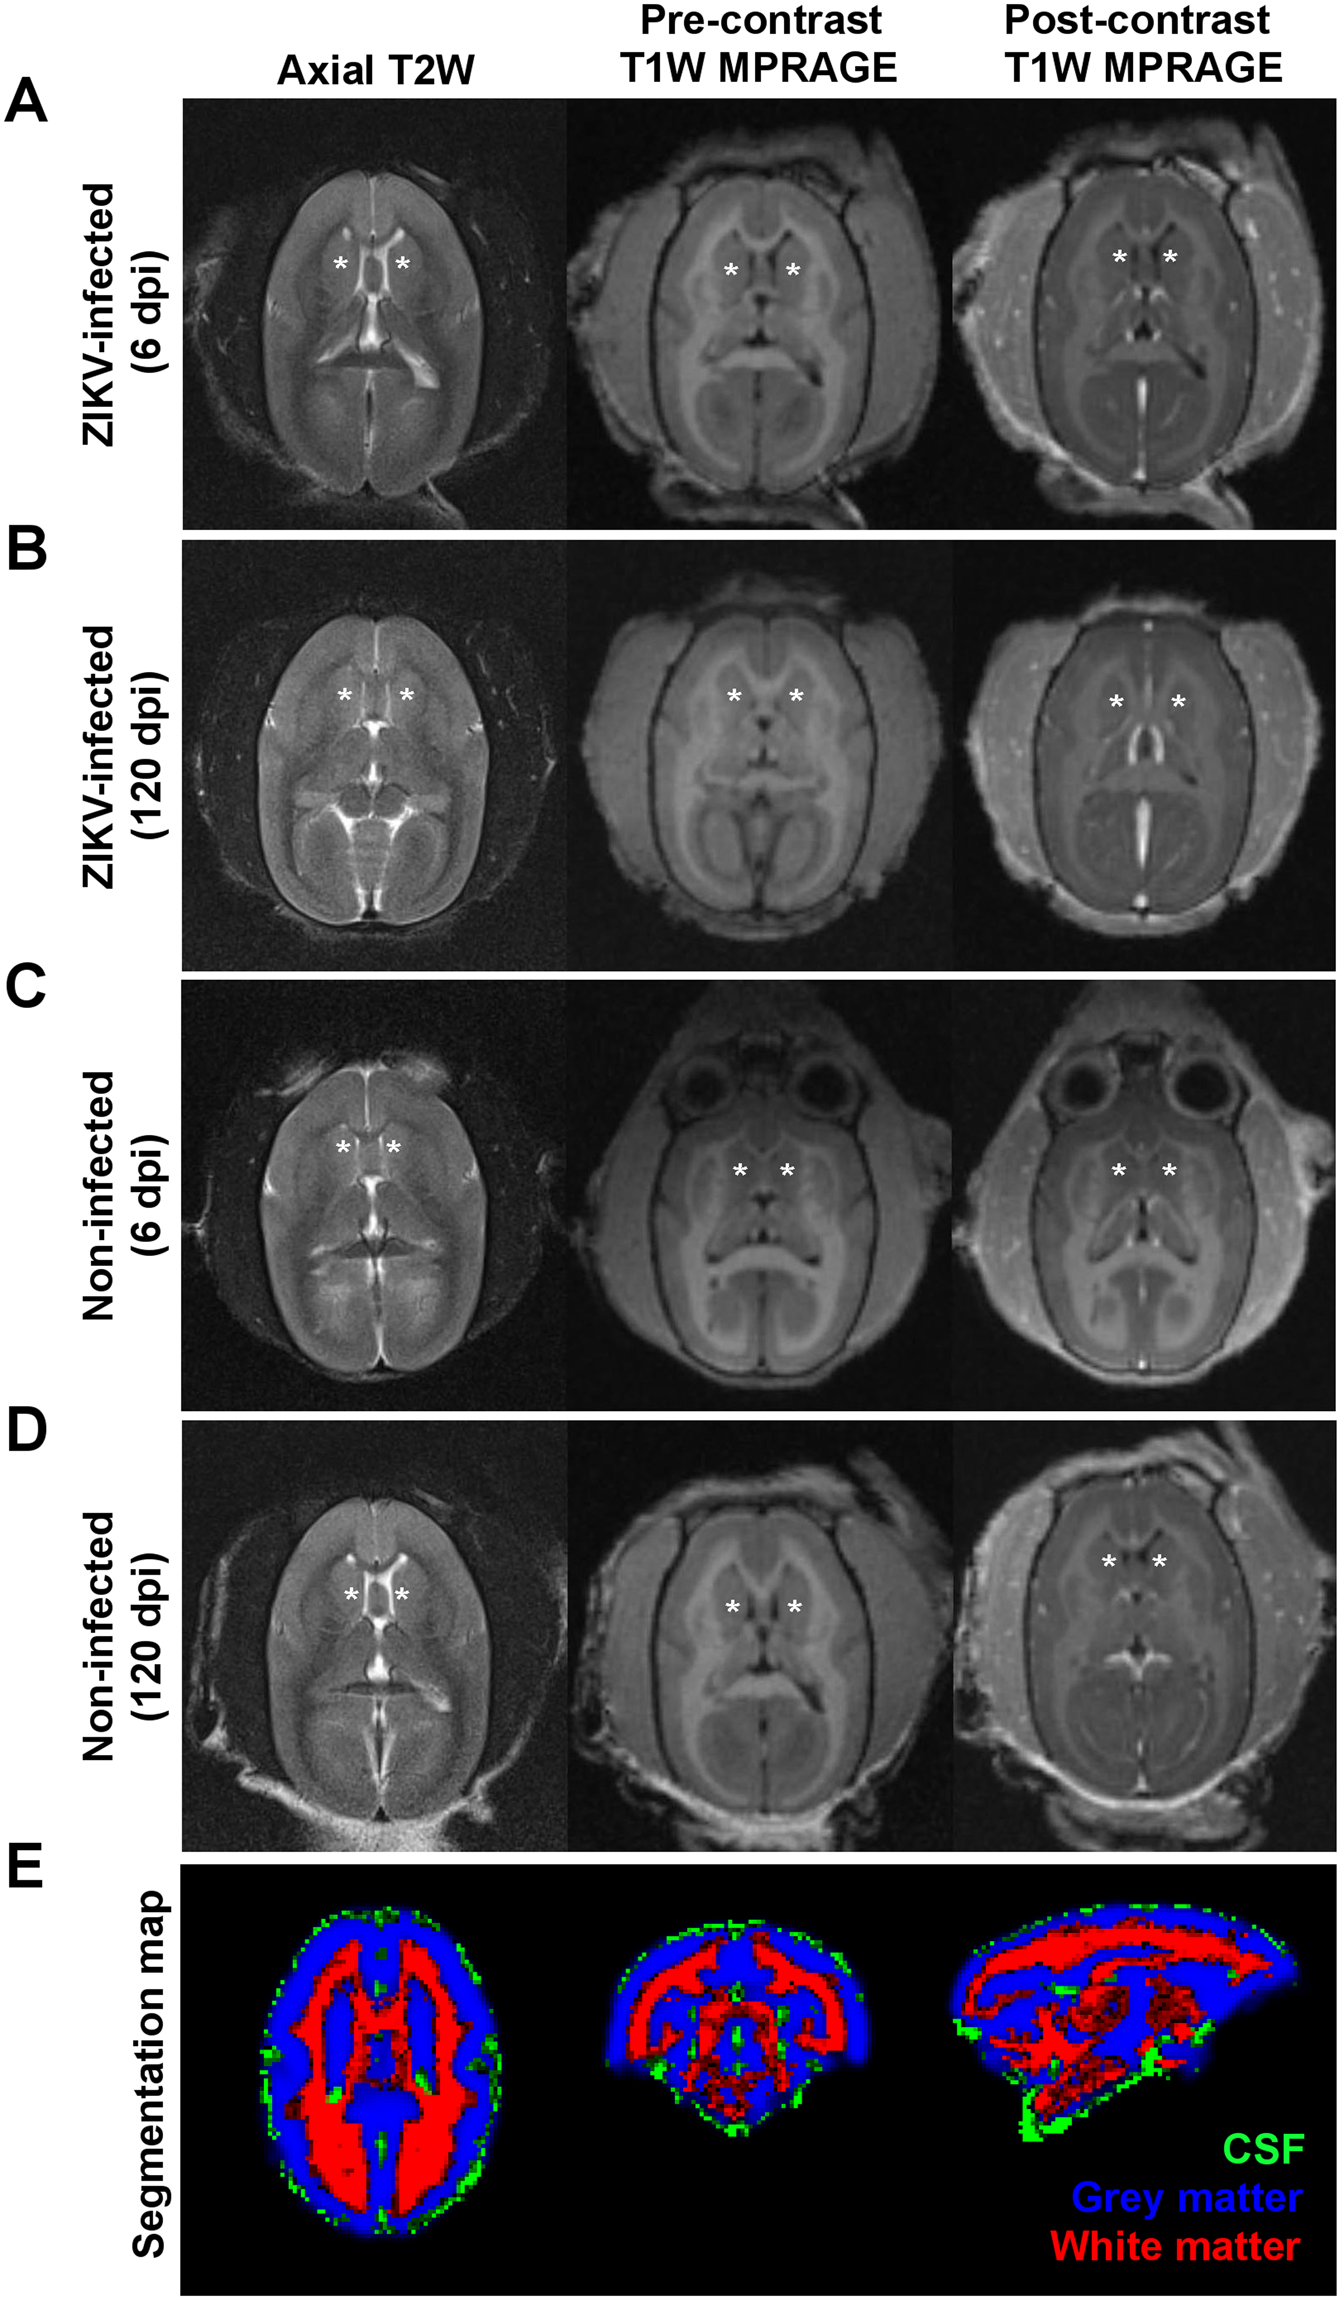

MRI brain images. (A–D) From left to right columns, axial T2-weighted fast spin-echo, pre- and post-contrast T1-weighted MPRAGE images of the marmoset brain at the level of the basal ganglia with asterisk (*) denoting the caudate nucleus. These represent (A,B) ZIKV-infected or (C,D) non-infected marmosets obtained at (A,C) 6 or (B,D) 120 dpi. No focal abnormality or pathological enhancement is seen in the ZIKV-infected brain. (E) Segmentation map of the marmoset brain for white, grey matter and cerebrospinal fluid (CSF).